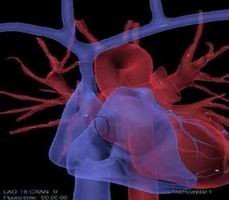

冠狀動脈介入手術(shù)模塊

可練習(xí)冠狀動脈支架手術(shù)的完整過程:造影診斷、導(dǎo)絲通過、導(dǎo)引導(dǎo)管的放置、預(yù)擴張、自擴張支架放置、后擴張、以及再造影等